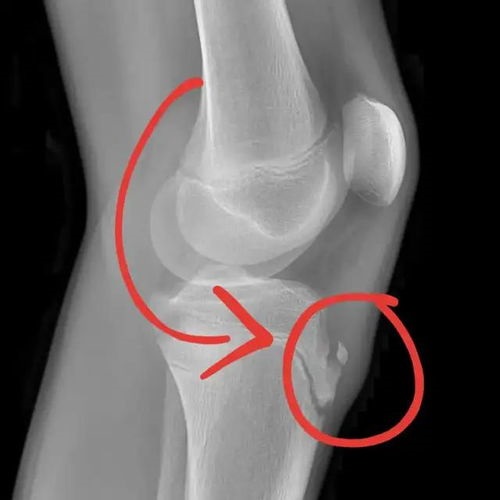

A doctor can usually diagnose Osgood-Schlatter’s disease based on a medical history and a physical examination. A healthcare expert may apply pressure to the tibial tubercle during the evaluation, which will be uncomfortable or painful for a child with the issue.

They may also ask the child to walk, run, jump, or kneel to see whether these actions aggravate the symptoms. They may also order X-rays to confirm the diagnosis and rule out other possibilities. The location of the pain in the tibial tuberosity also aids in differentiating Osgood-Schlatter disease from other illnesses.